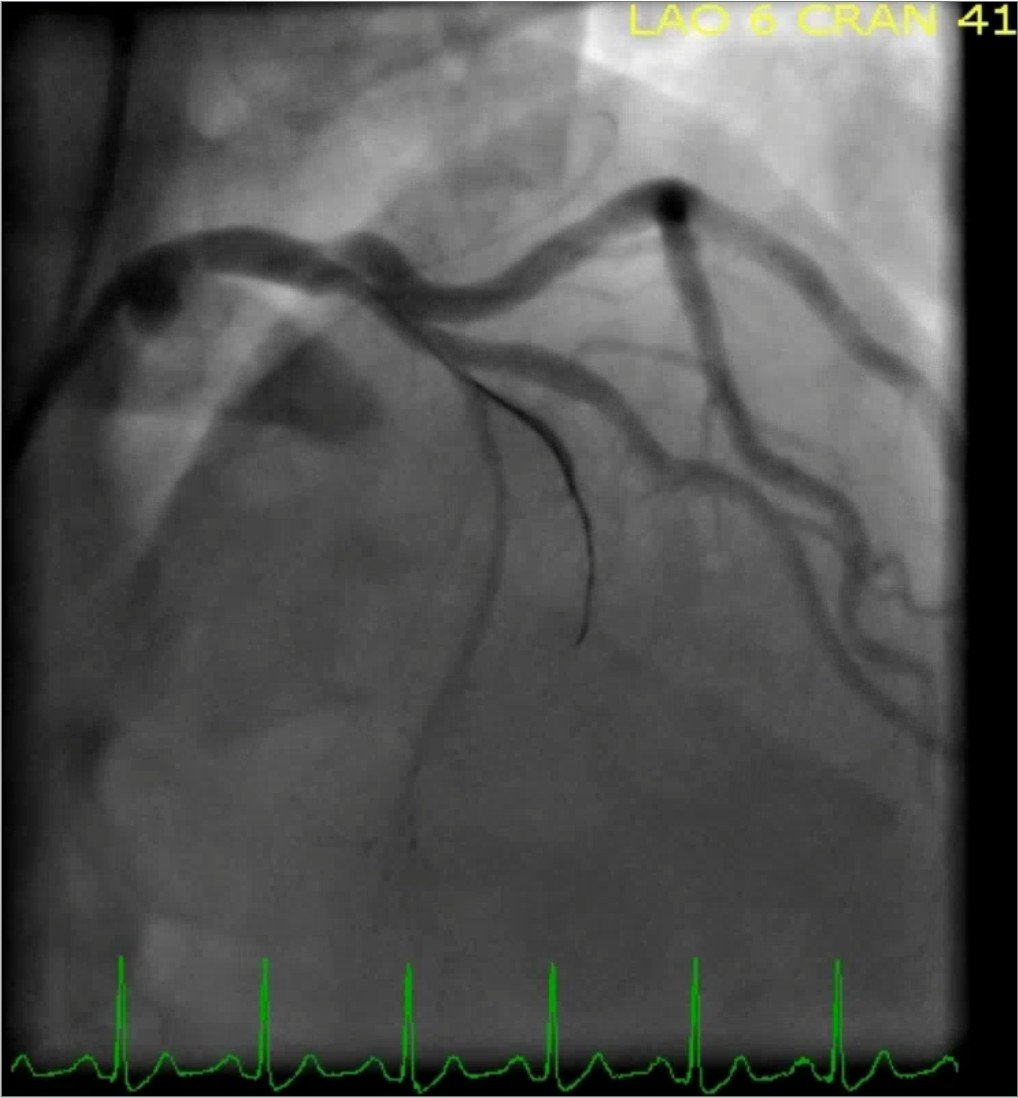

The cardiac catheterization revealed a thrombotic occlusion of the proximal to mid LAD (100% in-stent restenosis of the previously placed bare-metal stent). The patient underwent successful placement of one drug eluting stent with restoration of TIMI 3 flow. Here are the images from the cardiac cath:

Mid to distal-LAD in-stent stenosis with 100% occlusion and TIMI flow 0

LAD post-DES placement with TIMI 3 flow

The amount of territory supplied by this vessel becomes obvious here (and goes on for a few more frames below this still). None of this territory was perfused until this point.